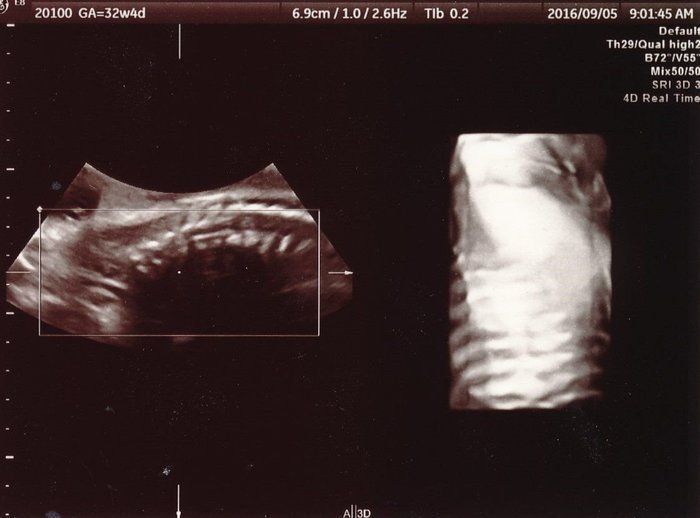

小吉さんの妊娠32週目のエコー写真

赤ちゃんの背骨と肋骨がしっかりとできていることが確認できました。「小さいのにちゃんとあるな、頑張っているな」と感動したのを覚えています。